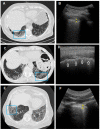

Transthoracic ultrasound (TUS) is a readily available imaging tool that can provide a quick real-time evaluation. The aim of this preliminary study was to establish a complementary role for this imaging method in the approach of interstitial lung diseases (ILDs). TUS examination was performed in 43 consecutive patients with pulmonary fibrosis and TUS findings were compared with the corresponding high-resolution computed tomography (HRCT) scans. All patients showed a thickened hyperechoic pleural line, despite no difference between dominant HRCT patterns (ground glass, honeycombing, mixed pattern) being recorded (p > 0.05). However, pleural lines' thickening showed a significant difference between different HRCT degree of fibrosis (p < 0.001) and a negative correlation with functional parameters. The presence of >3 B-lines and subpleural nodules was also assessed in a large number of patients, although they did not demonstrate any particular association with a specific HRCT finding or fibrotic degree. Results allow us to suggest a complementary role for TUS in facilitating an early diagnosis of ILD or helping to detect a possible disease progression or eventual complications during routine clinical practice (with pleural line measurements and subpleural nodules), although HRCT remains the gold standard in the definition of ILD pattern, disease extent and follow-up.